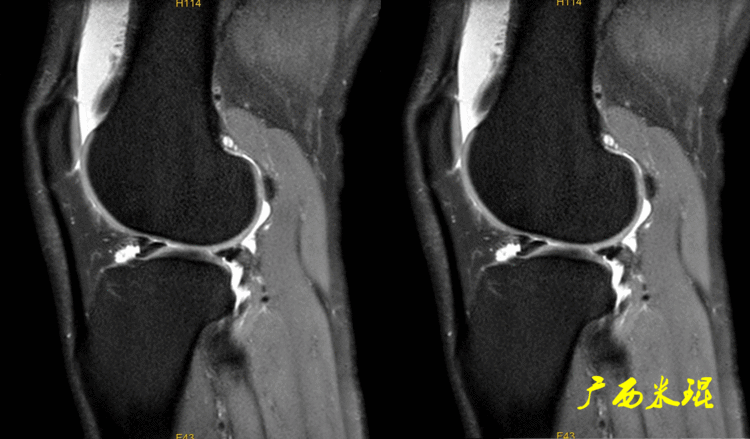

14、手术后半月板半月板手术后导致的半月板形态和信号的改变千变万化,有时候其改变可能在MR上比手术前还差,这种MR上的改变不代表手术存在问题,所以已故的冯华教授生前就经常说手术后的半月板MR很难评价。

下面矢状位MR是外侧半月板后角部分切除手术后,片上我们发现半月板后角部分缺失,半月板信号正常(因为手术前半月板没有退变)。

下面矢状位MR是内侧半月板后角水平撕裂部分切除手术后,半月板后角部分缺失,信号仍然不正常(因为手术前半月板已经有退变),真正的情况是关节镜下半月板外观是正常的,MR上看见的高信号影是半月板退变的Ⅱ级信号所致,由于手术切除面达退变的层面,MR上容易误诊为Ⅲ级信号。

下面矢状位MR是内侧半月板后角纵形撕裂缝合手术后,半月板外观完整,无分离,缝合处小片状稍高信号,这个高信号几乎不可能消失(半月板损伤痕迹永远存在)。

内侧半月板后角纵形撕裂缝合手术后,半月板外观完整,无分离,缝合处的线状稍高信号一般情况下也永久存在。

如同下面这张MR,左侧图像为手术前的,右侧图像为手术后的,术后病人疼痛等症状仍然存在,复查MR见外侧半月板前角分层,半月板前角的处理是有一定难度的,有经验的医生会考虑可能是手术者对前角的处理不够熟悉,没有通过另外的办法处理半月板前角的水平裂,不过也只能是猜测而已。所以,对于半月板术后的评估,症状的消失比MR重要!